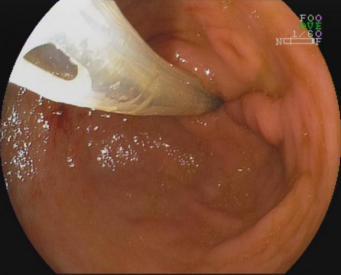

6.经口内镜下食管括约肌切开术(peroralendoscopicmyotomy,POEM)

POEM是治疗贲门失弛缓症的内镜新技术,基本取代传统的胸外科开胸食管肌切开术,成为首选的治疗方式。

贲门失弛缓症食管紧闭 食管粘膜切开建立隧道

食管肌切开 金属夹闭合切口